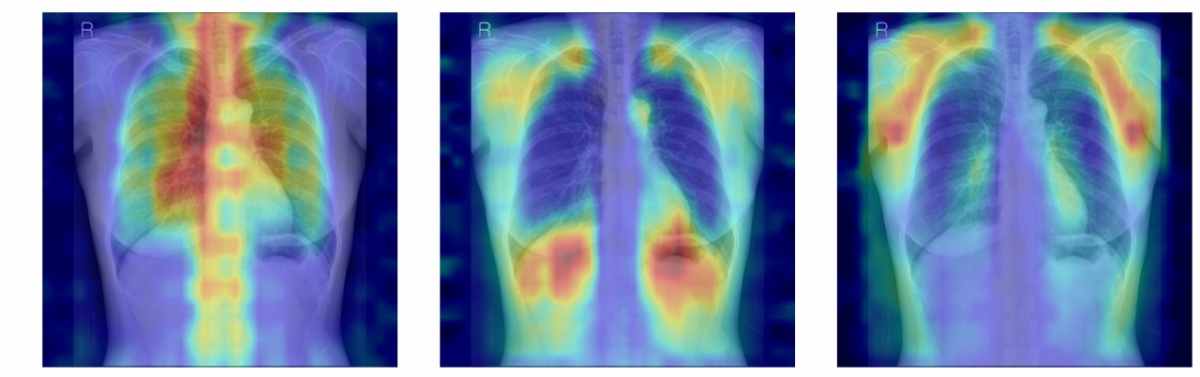

연구팀은 여기에 더해 AI가 실제로 어떤 뼈를 근거로 삼아 판단하는지까지 확인할 수 있도록 '설명 가능성' 평가 체계를 설계했다. 뼈를 모두 가린 상태에서 특정 뼈 부위를 추가해 성능이 얼마나 향상하는지 확인하는 '차단 분석 방식(Δbone)'과 Grad-CAM으로 나타난 AI의 주목 영역이 실제 뼈 위치와 얼마나 일치하는지를 계산하는 '유의성 지도 방식(IoUbone)'을 통해, AI가 임상적으로 중요한 뼈 구조를 근거로 판단하는지를 정량적으로 검증했다.

그 결과, DINOv2 모델에 LoRA 방식을 적용한 모델이 AUC 0.93(95% CI 0.92–0.94)로 가장 높은 예측 성능을 보였다. 이 모델은 뼈 구조 활용도가 가장 높고, 주목 영역의 타당성에서도 우수해, 예측력과 설명 가능성이 균형 있게 확보된 최적 모델로 평가됐다.